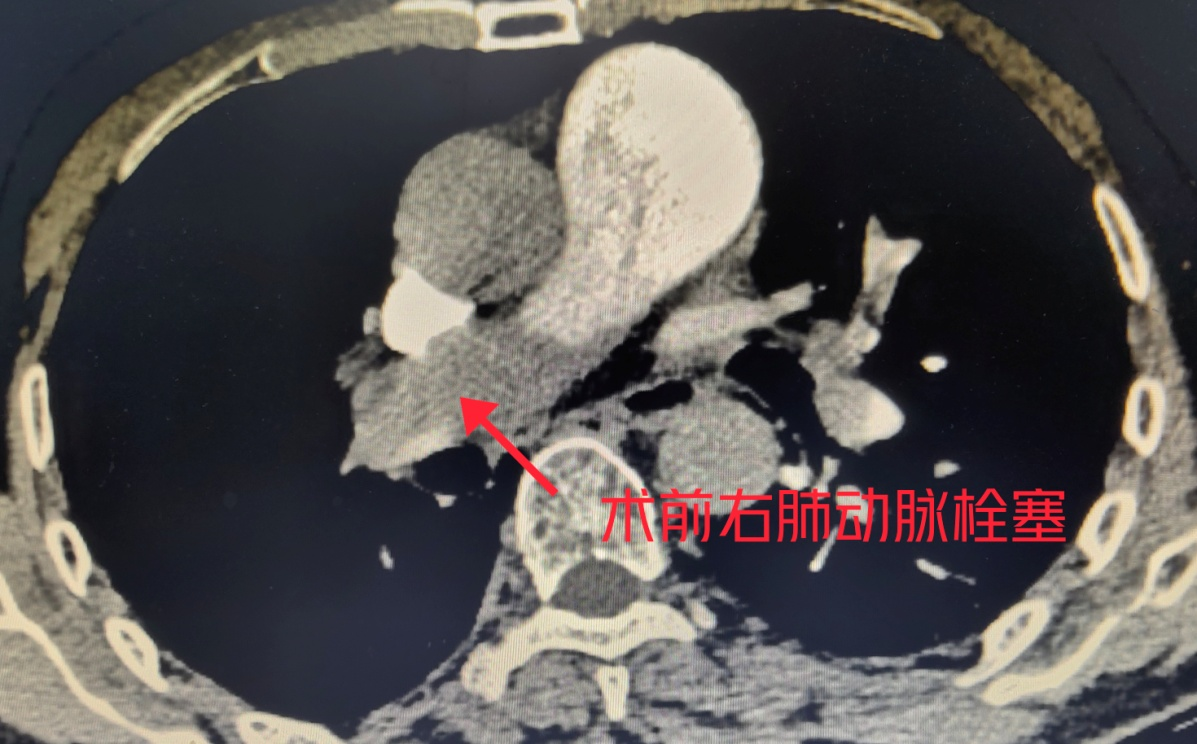

术前右肺动脉栓塞

市民老刘(化名)4天前突然出现左下肢肿胀,当时不以为意,不料昨日肿胀明显加重,行走后突然出现胸闷,喘不过气,甚至有窒息感。于是赶紧到广西壮族自治区南溪山医院血管外科就诊,接诊的血管外科副主任胡长付博士看老刘呼吸急促、胸闷、说话上气不接下气,经过详细了解病史,初步诊断老刘是因为左下肢深静脉血栓脱落至肺动脉,导致肺动脉堵塞,所以才出现以上症状。经过下肢静脉彩超及肺动脉增强CT检查,胡博士的诊断果然得到了验证。

老刘生命征极不平稳,大面积肺动脉栓塞随时有致死的风险。胡博士争分夺秒,立即为老刘进行了急诊介入下局部麻醉穿刺右股静脉经导管肺动脉溶栓术、下腔静脉滤器植入。